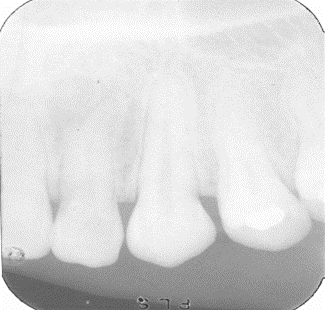

Filme Radiográfico Periapical

O filme periapical é indicado para avaliar dentes individualmente, incluindo coroa, raiz e tecidos periapicais.

Sua utilização é indispensável em casos de endodontia, periodontia e cirurgias apicais. Os tamanhos mais comuns são:

- Tamanho 0: indicado para odontopediatria.

- Tamanho 1: geralmente usado em incisivos.

- Tamanho 2: padrão para adultos, permitindo ampla visualização do dente e estruturas adjacentes.